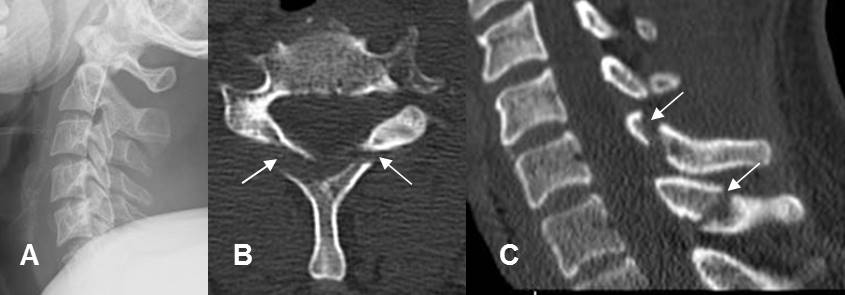

Fig 202. Fractura del paleador.

A: Rx lateral. No se aprecian alteraciones, pero solo son evaluables 5 cuerpos vertebrales.

B: TAC axial C: TAC reconstrucción sagital. Fracturas no desplazadas en las apófisis espinosas de C6 y C7.